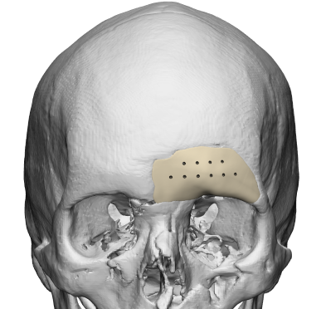

Las imágenes corresponden a un caso propio de un paciente para cirugía maxilofacial tercio medio.

CASO CLÍNICO

Paciente masculino, con un defecto de dimensiones aproximadas de 138.64×110.44mm el cual fue intervenido quirúrgicamente con excelentes resultados, un ejemplo de diseño con puente plano.